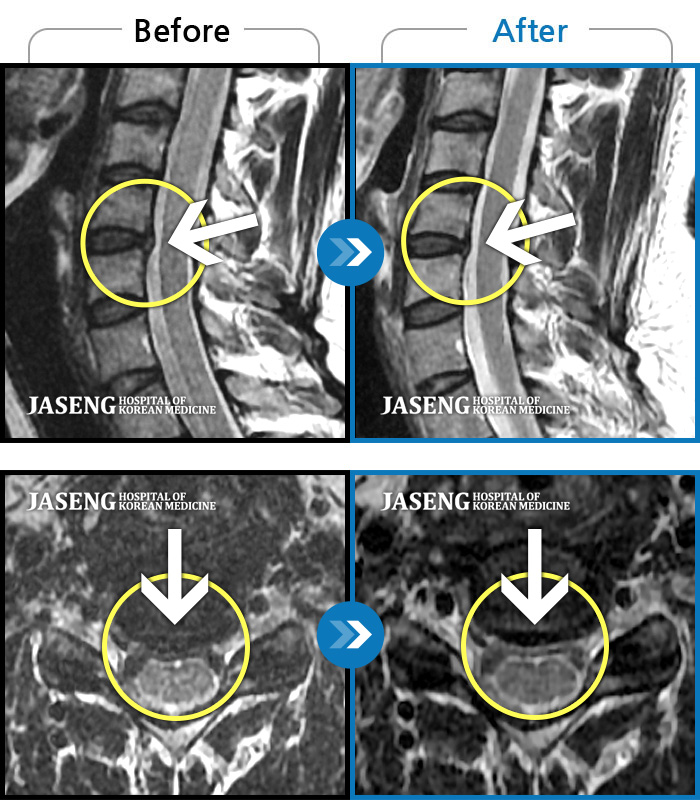

Before

After

처음 내원시 목에서 등으로 이어지는 통증 및 우측 팔 저림 증상이 심했고, 약간의 근력저하도 동반되어 일상생활이 어려운 상태였습니다.

2024.04.06 ~ 2024.11.16

목 통증과 새끼 손가락 저림 및 안정시에도 우측 어깨 통증 호소하여 내원하셨습니다.

2022.08.10 ~ 2024.11.08

좌측 승모근부터 견갑골까지 이어지는 통증, 좌측 상완 비증으로 내원하셨습니다.

2024.04.03 ~ 2024.10.24